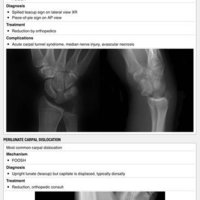

• Splints

• Trauma

• Ultrasound